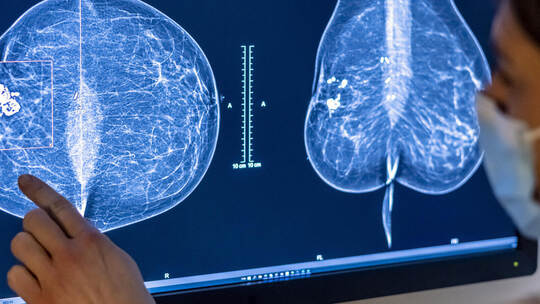

Schockdiagnose Krebs: Immer mehr Menschen in Pforzheim und dem Enzkreis betroffen – auch Jüngere

Pforzheim. Die Diagnose ist für die meisten Menschen ein Schock. Neben der Angst vor dem Tod kommen sofort viele Fragen auf: Wie geht es weiter? Wer hilft mir? Was passiert mit meiner Familie? Auch in der Region gehen diese Sorgen vielen Menschen durch den Kopf. Denn immer mehr Menschen erkranken hier an Krebs. Die Krankenhäuser und Beratungsstellen kennen die Ursachen dieser Entwicklung – und machen auch Hoffnung.

Sowohl das Helios Klinikum als auch das Siloah St. Trudpert Klinikum verzeichnen seit Jahren steigende Fallzahlen. Als Hauptfaktor für die Zunahme von Tumor-Neuerkrankungen nennen beide den demografischen